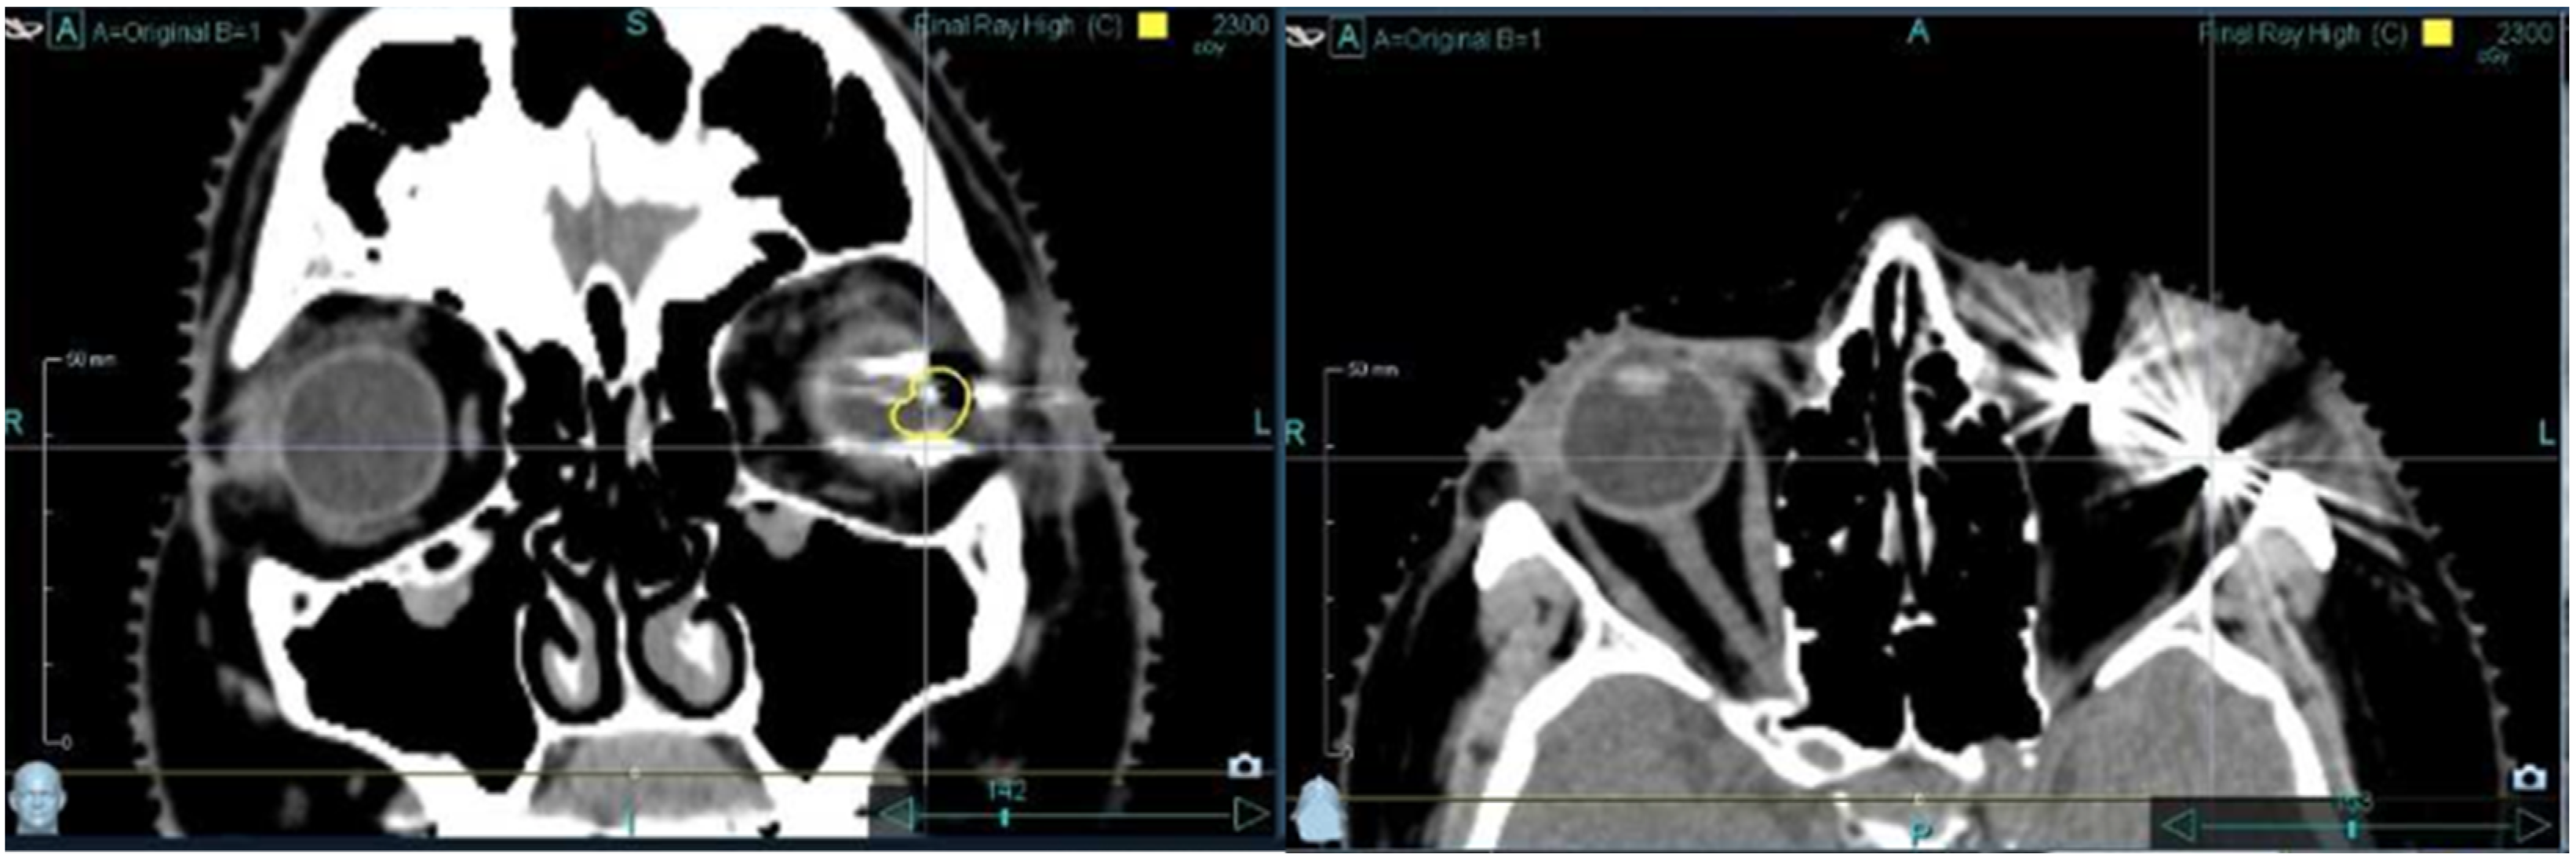

Nevertheless, the metallic TFMs have some disadvantages. These induce scattering artifacts in CT scans and X-rays and hence increase the uncertainty regarding the dose distribution of the radiation treatment. The artifacts also reduce the imaging quality and hinder the precise delineation and target localization of the tumor during treatment (Figure 1). In order to reduce these effects, others have already looked for alternative materials, but none of them have been successfully introduced into routine use until today [16,17,18,19].

Figure 1.

CT images of tantalum fiducial markers. Tantalum fiducial markers show huge scattering artifacts, which make the bulbus, and therefore, also the tumor, barely visible in some scans.